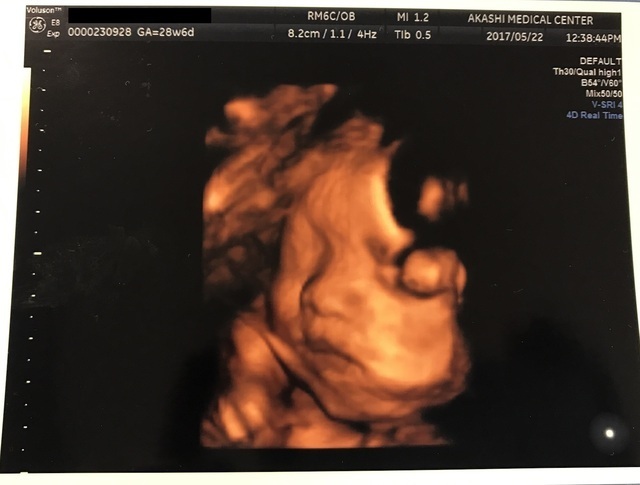

25週1日(25w1d・男の子)|紬 さん(24歳)

エコー写真撮影時のエピソード:

4Dエコーを見に大きな産婦人科へ行きました。あくびする姿を見れたり、手が5本ちゃんとあるのが確認できたり、データを持ち帰ることも出来たので改めて旦那とゆっくり見たり出来ました。凄く充実した時間であり、赤ちゃんの動く姿や可愛い仕草を見て安心できました。